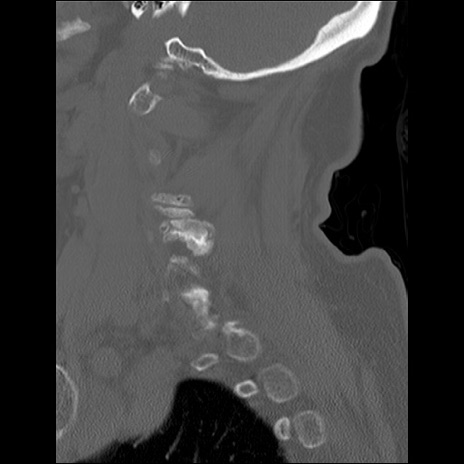

症例48 頚椎CT(矢状断像)

頚椎CT